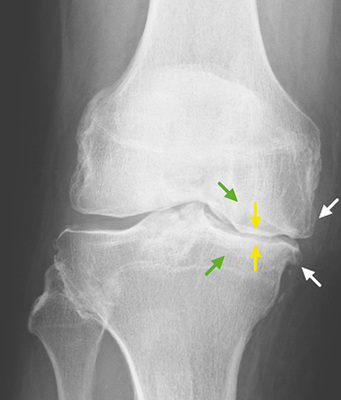

Konsensusempfehlung BK 2112 Merkmal „definiter“ Osteophyt

Ein definiter Osteophyt ist eine knöcherne Ausziehung einer Größe 2 mm ab antizipierter Knochenform des Gelenkrands (  Abb. 5 , Beispiele auch Nagaosa et al. 2000; Altman u. Gold 2007). Patellär sind nur die seitlichen Anbauten als relevant zu werten. Hier ist darauf zu achten, diese nicht mit Sehnenansatzverkalkungen oder Fibroostosen zu verwechseln (Freyschmidt et al. 1978).

Konsensusempfehlung BK 2112 Gelenkspalt-verschmälerung

Basierend auf Normwerte nach Lanyon (1998), der Gelenkspaltmessungen an 86 Frauen und 39 Männern ohne Kniebeschwerden und ohne Osteophyten durchgeführt hatte (Altersverteilung 40–75 Jahre, Durchschnittsalter 58 Jahre), einigte sich die Konsensusgruppe auf folgende Werte für eine vorliegende Gelenkspaltverschmälerung: siehe   Tabelle 2 für das Femorotibialgelenk und   Tabelle 3 für das Patellofemoralgelenk.